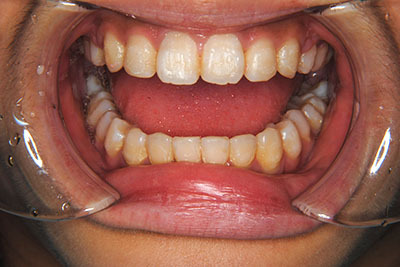

小学生高学年や中高生で矯正治療を考えている方へ

歯が乳歯から永久歯に生え変わった小学生高学年や、中高生でも矯正治療に手遅れということは全くありません。

成長中の顎の骨を矯正できたり、この時期の矯正はおとなになってから矯正治療を始めるよりも短期間で済むことがほとんどです。当院だとおおよそ1年で動的治療(マルチブラケット装置をつける期間)が終わることが多いです。